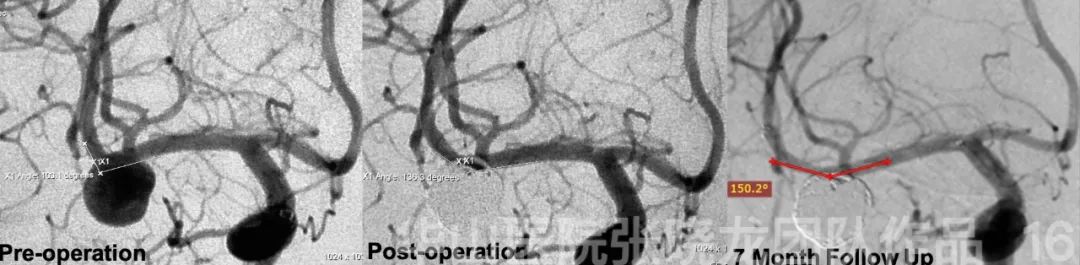

Figure 13. Parent artery angle increases from 103.1° to 136.3°.

Figure 15. Seven month follow up angiography shows no relapse of the aneurysm. The patient was symptom free.

Figure 16. The change of aneurysm angle from span-operation to follow up: 103.1°→ 136.3°→150.2°.